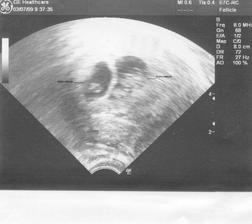

16.6. - hcg 6696, na utz jeden váček

25.6. na utz dva váčky, zatím 1 srdíčko.